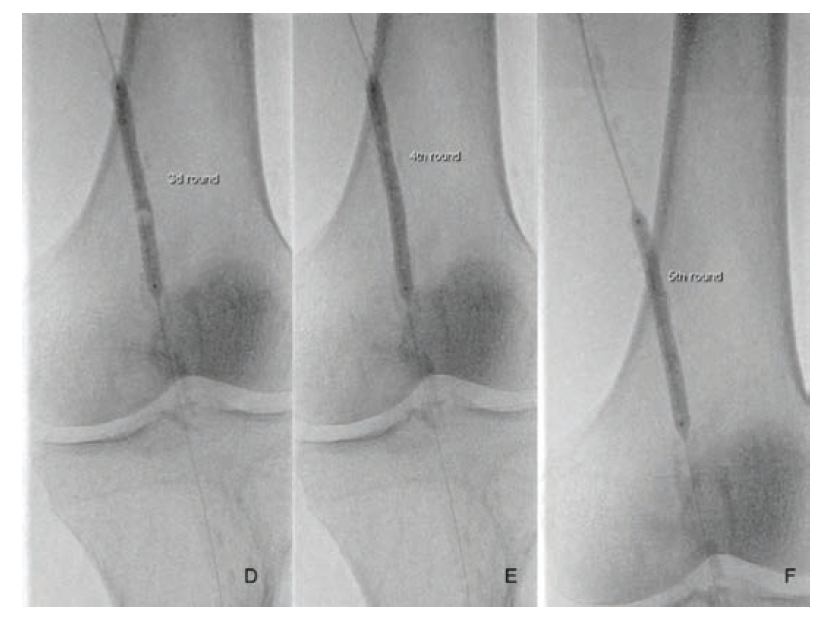

Under local anesthesia, left antegrade femoral arterial access was obtained using ultrasound guidance. After the insertion of a short 6 Fr arterial sheath (Terumo), a diagnostic angiogram was performed using the Angiodroid carbon dioxide (CO2) injector (San Lazzaro di Savena, Italy). This confirmed the preprocedural duplex ultrasound findings (Figure 1). A Choice PT 0.014 floppy wire (Boston Scientific) and a Quick-Cross support catheter (Phillips) were used to cross the lesion. After crossing the lesion, a vessel preparation with endovascular lithoplasty (Shockwave Medical, Fremont, US) was performed using a 5 × 60 mm catheter inflated to 4 atm and activated. After delivering 30 pulses, the balloon was inflated to the reference vessel diameter for an additional 120 seconds. The lithoplasty was activated an additional 6 times after repositioning of the catheter in order to treat the entire lesion from “healthy to healthy,” delivering a total of 180 pulses. An antirestenotic therapy with a drug coated balloon (DCB) (5 ×120 mm, In.Pact Admiral, Medtronic) was applied following the plaque modification. The final angiography did not show any residual stenosis, local dissection, or distal embolization. The procedure was completed with the use of 10 mL contrast medium, and the patient was discharged the following day.